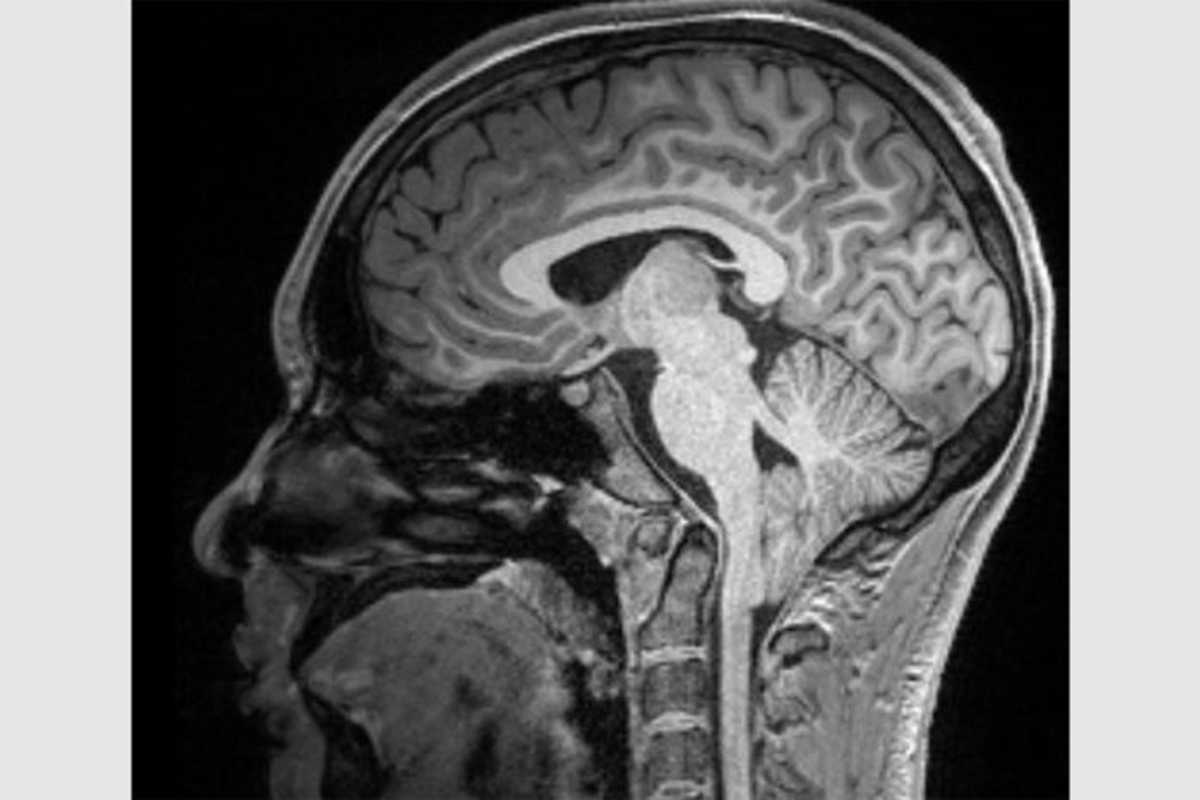

Roughly 4% of the population is affected by a congenital brain malformation that has eluded researchers’ efforts to find causes and treatments. For the condition, Chiari type-1 malformation, the diagnosis is straightforward: the lower part of the brain, known as the cerebellum, protrudes at least five millimeters through the gap in the skull that connects to the spinal cord.

There’s no one known cause for Chiari type-1, and the symptoms it can cause are unpredictable. The most common problems include chronic headaches, difficulty swallowing and decreased muscle strength, as well as syringomyelia, a condition that occurs when a cyst forms in the spinal cord. Sometimes these symptoms occur in combination, or singly. In most cases, people can live their whole lives with no ill effects. The breadth of Chiari type-1 presentations has made it difficult for physicians to develop a consistent treatment protocol for their patients.